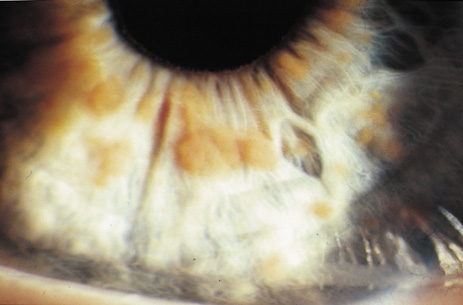

Lisch nodules are hamartomas (a tumor involving only those tissue elements normally found at the involved site) of the iris pigment epithelium. They are dome-shaped discrete lesions, are typically light brown in color, and may also be found in the angle.38 Lisch nodules appear earlier (33% at 2.5 years, 50% at 5 years of age)39 than neurofibromas. They are benign and can help to confirm diagnosis in children who may have café au lait spots as the only other clinical finding. Lisch nodules are present in nearly all adults with NF139,40 but are rare in NF2 (Fig. 3).41,42 Diffuse nodular iris nevi (also known as iris mamillations) should not be confused with Lisch nodules. Its clinical significance is not well established.43,44

Fig. 3. Neurofibromatosis type 1: Lisch nodules. These are hamartomas of the iris pigment epithelium. Lisch nodules are present in nearly all adults with NF1,39,40 but are rare in NF2.41,42

Retinal hamartomas affect about 10% to 20% of patients (8% in one study91and 22% in another98) and may be associated with a more severe phenotype of NF2.91,98 Combined pigment epithelial and retinal hamartomas (CPERH) and epiretinal membranes have been reported.101–103 Lisch nodules are rare in NF2. The absence of Lisch nodules, in association with the presence of posterior subcapsular or cortical cataracts (Fig. 8) may aid the differentiation of NF1 and NF2.97,104,105 Optic nerve sheath meningiomas may cause significant visual impairment in the first years of life (Table 2).84,106

Fig. 8. Neurofibromatosis type 2: cortical wedge cataract. Lens opacities (cortical wedge and posterior subcapsular cataract) may be the initial manifestation of disease in 10%.98